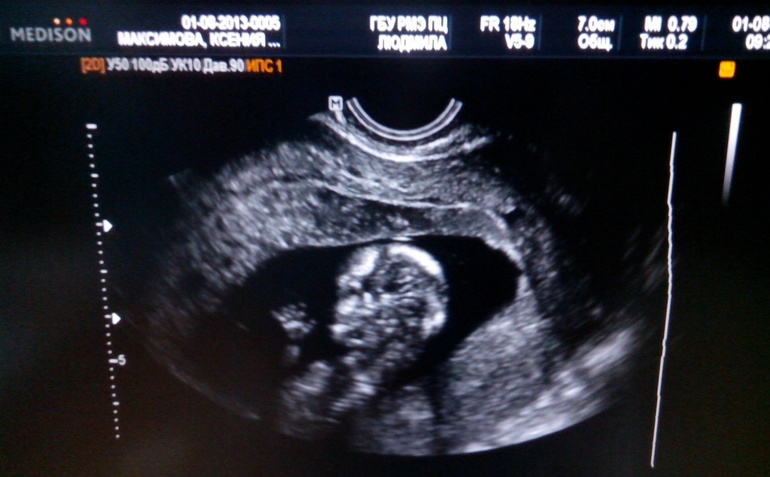

Пришли мы с малышом на УЗИ бесплатно, по направлению в наш роддом. Там хороший ремонт евро сделали, аппараты новые. Долго ждать не пришлось, меня сразу вызвали . Узи делала женщина такая хорошая, добрая, спокойно не торопясь всё объяснила . Делала долго, смотрела хорошо. Передо мной висел большой монитор. В первые секунды я затаила дыхание, и вот: мой малыш, такой кроха, но у него все на месте))) Барахтается шесть см моего счастья, ручки ,ножки, вот, ротик, носик... Вот 5 пальчиков ))) Я еле сдерживаю слезы.. такое счастье!!!!

Замеряли воротниковое пространство, включили сердечко послушать,ЧСС 164, КТР точно 64,48 срок поставили 12+6, а по месячным 12+3))) не отстаем))) Вообщем, сказали, все хорошо))

Ах да, сказали, что 70% у нас родится доченька))) мы очень рады)))

А вот и фото:

Машет маме ручкой))))